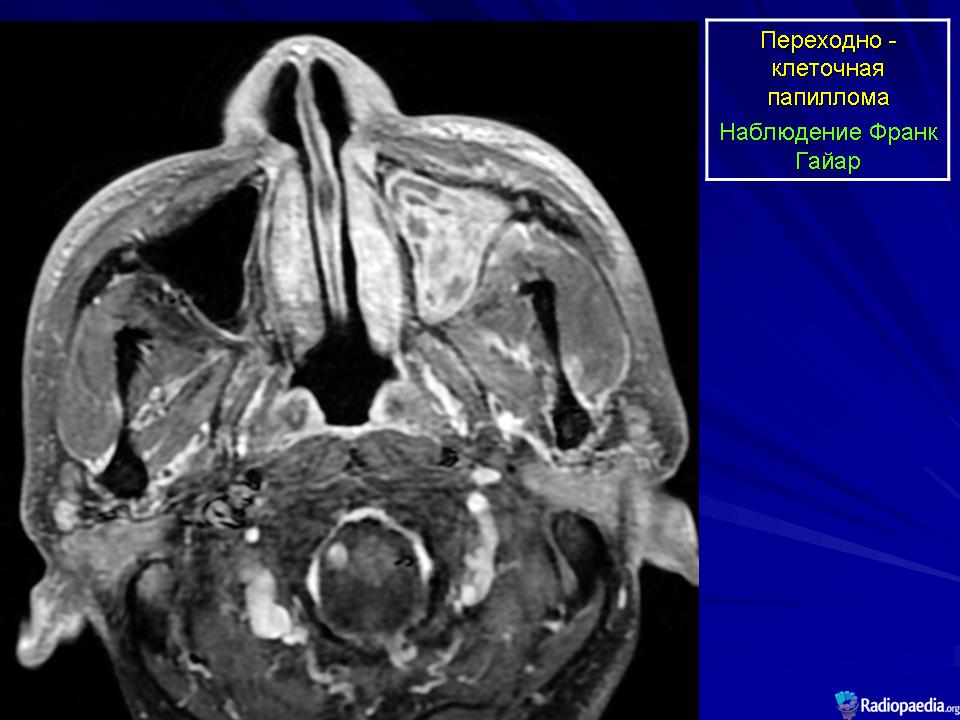

Переходно-клеточная папиллома.

Инвертированная переходно-клеточная папиллома (син.: папиллома Шнейдера, эпителиальная папиллома, сосочковая фиброэпителиома, папиллярный синусит, цилиндроклеточная папиллома, папиллома из респираторного эпителия) — редкая, но характерная для полости носа и его синусов доброкачественная опухоль, составляющая около 0,5 % от находок всех новообразований носа. Она чаще встречается у мужчин, преимущественно на пятом-шестом десятилетии жизни. Обычно односторонняя, эта опухоль бывает одиночной и множественной. Как правило, она возникает на боковой стенке полости носа, а также в околоносовых пазухах: гайморовой полости, решетчатом лабиринте, изредка в лобной и основной пазухах. При сочетанном поражении локализацию первичного узла установить практически невозможно. Из полости носа опухоль может врастать в околоносовую пазуху и наоборот. Пациенты обычно жалуются на заложенность носа, выделения, носовые кровотечения, боль в области лицевого нерва. Иногда в зоне опухолевого роста происходит разрушение костной ткани. Чаше всего страдают стенки гайморовой пазухи. Но опухоль может расти и в других направлениях, разрушая стенку неба, стенки глазницы или кости основания черепа. Рецидивы опухоли могут возникать через 5—10 лет. Примерно у 5% больных инвертированная переходно-клеточная папиллома способна превращаться в рак после долголетнего доброкачественного течения. Метастазы не наблюдаются.

Макроскопически мягкая, со складками, опухоль имеет дольчатое, сосочковое строение, шероховатую поверхность. Цвет ее ткани варьирует от розового до желто-красного. Инвертированная переходно-клеточная папиллома рецидивирует в 75 % случаев, если проведена локальная эксцизия. Для оптимального лечения при локализации опухоли на боковой стенке носовой полости рекомендуется боковая ринотомия и срединная резекция верхней челюсти. Если такая папиллома малигнизируется, то ее клиническое течение становится более агрессивным.